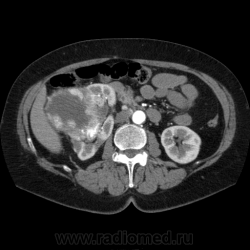

Солитарное кистовидное образование правой почки с неравномерно утолщенными стенками, у узлами в капсуле, накапливающими контраст. Фасция Гарота справа тяжистая. По классификации - киста 4-й категории, крайне велика возможность малигнезации. Может, показалось вовлечение парааортальных лимфоузлов?

В 1986 г. M.A. Bosniak создал “рабочую” классификацию кистовидных образований почек, которая позволяет предположить доброкачественность или злокачественность кистозных образований при распределении их по радиологическим критериям на 4 основные категории. Образования I и II категорий являются заведомо доброкачественными и поэтому нуждаются в динамическом наблюдении или, по показаниям, в лечебной пункции со склеротерапией под контролем УЗИ или КТ. Образования III категории могут быть как доброкачественными, так и злокачественными, а образования IV категории – кистозные почечноклеточные раки.

IV категория – поражения явно злокачественные, обычно кистозные почечно-клеточные карциномы. Основными симптомами кистозной опухоли при КТ являются: неправильная форма кисты, негомогенность структуры образования с участками некроза, деформация почки, нечеткая граница между кистой и паренхимой почки, плотностные показатели могут быть выше, чем в кистах (+20…+40 Н), т.е. близкие к плотности почечной паренхимы. Капсула имеет неравномерную толщину, часто обызвествлена по периферии. Возможна визуализация дополнительных фокусов образования (кажущееся увеличение образования в размерах и изменение его конфигурации) после введения контрастного вещества. Но самым важным симптомом является увеличение плотности внутреннего содержимого после внутривенного введения контрастного вещества. Часто на серии срезов удается выявить эндофитные гребневидные фестончатые разрастания, выступающие в просвет кистозной полости. Особенно хорошо этот мягкотканый васкуляризированный компонент опухоли проявляется при внутривенном контрастировании

Всё верно, я тоже пользуюсь данной классификацией по Босняку, кистозно-солидное образование правой почки я отнёс к 4 категории, нужно отметить, что преобладает кистозный компонент, но солидный компонент довольно приличный и значительно накапливает контрастное вещество до 80-90HU, четко капсулу образования не отграничить. Ко всему этому в паренхиматозную фазу четко дифференцируются единичные парааортальные и паракавалльные л/узлы. С большей степенью вероятности в данном случае cr почки. Пациентка на следующей неделе будет госпитализирована для верификации.

Описание изменений, выявленных при микроскопическом исследовании: опухоль представлена крупными альвеолярными структурами из светлых, оптически пустых клеток с мелкими гиперхромными ядрами, опухоль частично инфильтрирует капсулу почки, полностью прорастает стенку почечной лоханки, образуя полиповидные структуры. Одиночные опухолевые эмболы в сосудах почки. Отдельно присланный узел представлен тканью почки с опухолевым узлом, строение которого соответствует выше описанной опухоли. В воротах почки патологических образований не найдено. Во всех исследованных лимфоузлах (6 шт.) метастазы опухоли с замещением всей ткани лимфоузлов.

Патоморфологическое заключение: массивный светлоклеточный почечно-клеточный рак почки с частичной инфильтрацией капсулы, прорастанием в ЧЛС, опухолевыми эмболами в сосудах, множественными метастазами в забрюшинные лимфоузлы (6 шт